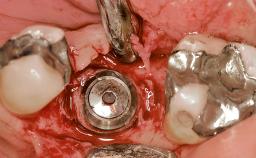

Early Placement of an Implant in a Maxillary Right Central Incisor Site

This 41-year-old female patient was referred to the clinic for the replacement of the right central incisor, since the tooth had developed a root fracture in the long axis that made extraction necessary. The healthy, non-smoking patient was first seen with the tooth still in place. A detailed Esthetic Risk Assessment was performed.The patient was worried about her dental esthetics and had high expectations for a successful treatment outcome from an esthetic point of view. The patient had a medium lip line that displayed parts of the gingiva in the anterior maxilla upon smile.